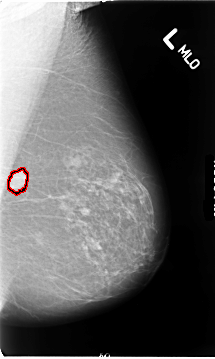

Digital Database for Screening Mammography

Volume: cancer_01 Case: B-3081-1

B_3081_1.LEFT_MLO

DATE_OF_STUDY 18 10 1994

PATIENT_AGE 71

FILE: B_3081_1.LEFT_MLO.OVERLAY

TOTAL_ABNORMALITIES 1

ABNORMALITY 1

LESION_TYPE MASS SHAPE OVAL MARGINS SPICULATED

ASSESSMENT 4

SUBTLETY 5

PATHOLOGY MALIGNANT

TOTAL_OUTLINES 1

BOUNDARY